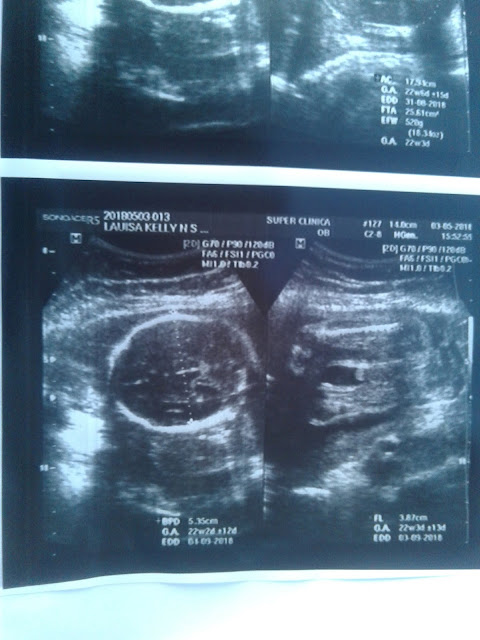

US Morfológica de 2 Trimestre

E fizemos a tão aguardada US morfológica de 2 trimestre e dessa vez o papai conseguiu ir também.

Pedro Henrique não estava muito a fim rs e resolveu ficar em posição transversa, ou seja cabeça, pra cima e pés pra baixo.

Dessa vez fiz com um médico e ele ficou tímido, faço todas as minhas US com minha Dra. Katia mas dessa vez infelizmente ela teve um contratempo e só iria atender em 15 dias, então a solução foi fazer com outro.

Vamos aos dados:

• Peso: 520 g

• Tamanho: 26,6 cm aproximadamente levando em conta o tamanho do fêmur.

• Placenta: 2,6 cm de espessura (grau  0)

• Todos os órgãos estão se desenvolvendo da forma correta. Não foi detectada nem uma alteração.

• Gravidez simples com idade gestacional estimada em 22 semanas e 04 dias.